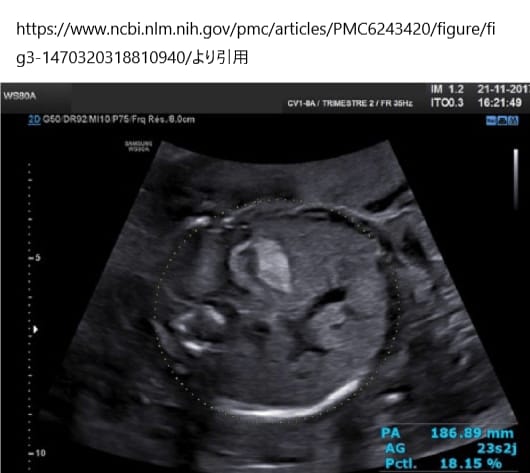

胎児高輝度腸管は、妊娠第2三半期(中期)の超音波検査で認められた胎児腸のエコー強度(明るさ)の増加を指す。高エコー(高輝度)とは、周波数5MHz以下の経腹トランスデューサーを用い、高周波帯をオフにし、ゲインを低くして、腸が骨と同じくらい明るく見えることをさす。周波数が高いトランスデューサや高周波によって、腸が高エコーではないにもかかわらず、高輝度に見えることがあるため、重要である。

胎児高輝度腸管は一過性で、7割程度の胎児で薄くなったり消えたりするが、嚢胞性線維症、先天性感染、羊膜内出血、胎児発育不全、消化管疾患など、さまざまな胎児および妊娠合併症と関連している可能性もある。胎児発育不全との関係性もあるため、胎児の成長を評価するために妊娠第3期(後期)のフォローアップ超音波検査が推奨される。